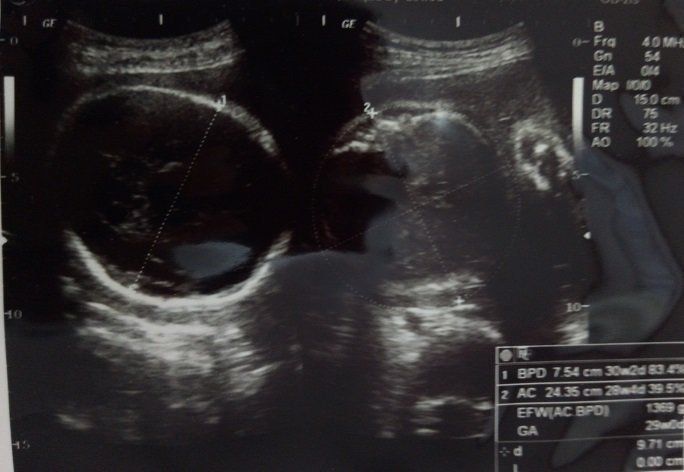

妊娠28週のエコー写真 赤ちゃんの推定体重1369g

この頃は足がつりやすく、明け方のこむら返りで飛び起きる毎日を送っていました。